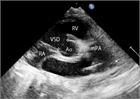

1. 心室中隔欠損は、欠損孔の部位により、膜性周囲部(perimembranous)、筋性部(muscular)、漏斗部または肺動脈弁下部(subarterial)に分類され、自然歴、手術適応が各々異なるため、部位診断は重要である。

1. 心室中隔欠損は自然閉鎖する場合もあるが、心不全症状を有する、あるいは肺高血圧を合併する場合、漏斗部欠損で大動脈弁の逆流を呈する場合は、外科手術の適応となる(推奨度1)。Eisenmenger症候群を呈すると手術適応がなくなるので、その前に適切な治療時期を逃さないことが大切である。